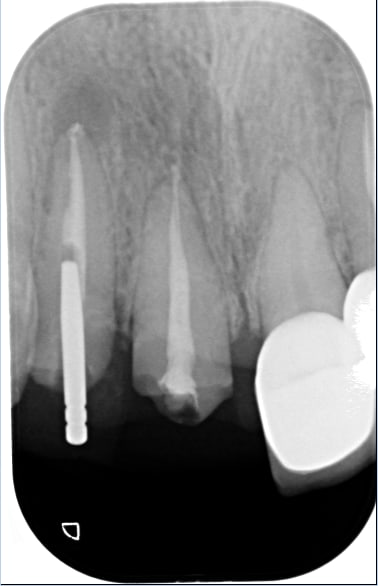

le meme genre de cas avant et apres le jour de la pose

plus tard la papille s'est recrée .